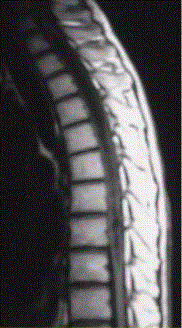

问题 患者女,45岁,胸部不适。影像学检查结果如下图所示。 病变的诊断为

选项 A.星形细胞瘤 B.室管膜瘤 C.脊髓空洞 D.髓内寄生虫 E.成血管细胞瘤 F.脊髓内转移瘤

答案 E